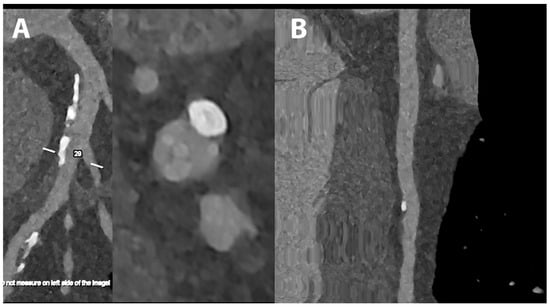

5.4. Coronary Artery Stenting

- Mannil, M.; Hickethier, T.; von Spiczak, J.; Baer, M.; Henning, A.; Hertel, M.; Schmidt, B.; Flohr, T.; Maintz, D.; Alkadhi, H. Photon-Counting CT: High-Resolution Imaging of Coronary Stents. Investig. Radiol. 2018, 53, 143–149. [Google Scholar] [CrossRef]

- Symons, R.; De Bruecker, Y.; Roosen, J.; Van Camp, L.; Cork, T.E.; Kappler, S.; Ulzheimer, S.; Sandfort, V.; Bluemke, D.A.; Pourmorteza, A. Quarter-millimeter spectral coronary stent imaging with photon-counting CT: Initial experience. J. Cardiovasc. Comput. Tomogr. 2018, 12, 509–515. [Google Scholar] [CrossRef] [PubMed]

- Petritsch, B.; Petri, N.; Weng, A.M.; Petersilka, M.; Allmendinger, T.; Bley, T.A.; Gassenmaier, T. Photon-Counting Computed Tomography for Coronary Stent Imaging: In Vitro Evaluation of 28 Coronary Stents. Investig. Radiol. 2021, 56, 653–660. [Google Scholar] [CrossRef] [PubMed]

- von Spiczak, J.; Mannil, M.; Peters, B.; Hickethier, T.; Baer, M.; Henning, A.; Schmidt, B.; Flohr, T.; Manka, R.; Maintz, D.; et al. Photon Counting Computed Tomography With Dedicated Sharp Convolution Kernels: Tapping the Potential of a New Technology for Stent Imaging. Investig. Radiol. 2018, 53, 486–494. [Google Scholar] [CrossRef] [PubMed]

- Rajagopal, J.R.; Farhadi, F.; Richards, T.; Nikpanah, M.; Sahbaee, P.; Shanbhag, S.M.; Bandettini, W.P.; Saboury, B.; Malayeri, A.A.; Pritchard, W.F.; et al. Evaluation of Coronary Plaques and Stents with Conventional and Photon-counting CT: Benefits of High-Resolution Photon-counting CT. Radiol. Cardiothorac. Imaging 2021, 3, e210102. [Google Scholar] [CrossRef] [PubMed]

- Boccalini, S.; Si-Mohamed, S.A.; Lacombe, H.; Diaw, A.; Varasteh, M.; Rodesch, P.A.; Villien, M.; Sigovan, M.; Dessouky, R.; Coulon, P.; et al. First In-Human Results of Computed Tomography Angiography for Coronary Stent Assessment With a Spectral Photon Counting Computed Tomography. Investig. Radiol. 2022, 57, 212–221. [Google Scholar] [CrossRef] [PubMed]

- Bratke, G.; Hickethier, T.; Bar-Ness, D.; Bunck, A.C.; Maintz, D.; Pahn, G.; Coulon, P.; Si-Mohamed, S.; Douek, P.; Sigovan, M. Spectral Photon-Counting Computed Tomography for Coronary Stent Imaging: Evaluation of the Potential Clinical Impact for the Delineation of In-Stent Restenosis. Investig. Radiol. 2020, 55, 61–67. [Google Scholar] [CrossRef] [PubMed]